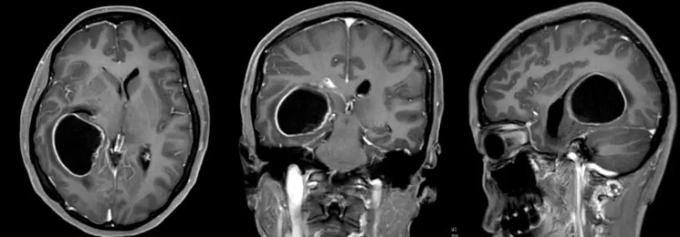

Kết quả chụp chiếu trước phẫu thuật của bệnh nhân Lâm. Ảnh: Ycwb

Kết quả chụp CT và CTA (cắt lớp vi tính mạch máu não) ban đầu phát hiện một khối choán chỗ lớn vùng thái dương – đỉnh – chẩm phải, kèm dấu hiệu đột quỵ và xuất huyết ngay trong khối u. Bác sĩ dùng thuốc chống phù não nhưng tình trạng người bệnh vẫn nguy kịch. Bệnh viện tuyến dưới nhanh chóng chuyển cô đến Bệnh viện Não 39 Quảng Đông ngay trong đêm.

Bác sĩ Đặng Thiếu Dũng tiếp nhận Lâm trong tình trạng nôn mửa liên tục và lơ mơ. Kết quả MRI xác nhận khối u gây não úng thủy. Êkíp khoa Ngoại thần kinh VII lập tức hội chẩn và quyết định phẫu thuật cắt bỏ khối u. Trưởng khoa Ngô Thái Hoa trực tiếp bóc tách hoàn toàn khối u dọc theo vùng biên tổn thương, đồng thời bảo tồn nguyên vẹn cấu trúc não thất bên. Suốt ca mổ, các bác sĩ dùng hệ thống điện sinh lý thần kinh giám sát liên tục nhằm đảm bảo độ chính xác cao nhất.